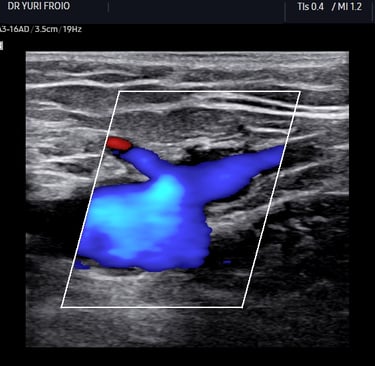

Ultrassom: ondas sonoras criam imagens das veias.

Doppler: identifica a direção e velocidade do sangue (cores no aparelho indicam fluxo normal ou alterado).

O Doppler emite sons e mostra cores no monitor (fluxo sanguíneo).

O Que o Doppler Revela Sobre Suas Varizes?

Mapa Venoso: localização exata das veias doentes.

Grau de Refluxo: se há sangue retornando (principal causa de varizes).

Coágulos (trombose): risco de complicações graves.

Função Valvar: se as válvulas das veias estão funcionando.